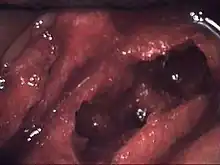

![]() | |

| Osteonecrosis of the jaw of the upper left jaw in a patient diagnosed with chronic venous insufficiency | |